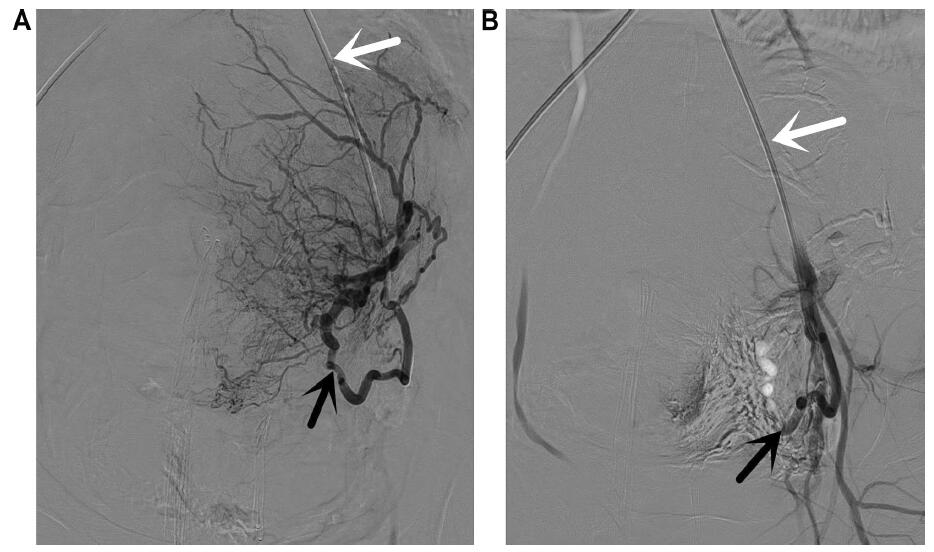

Figure 2.— First episode of embolization. A: Catheterization of the left uterine artery (black arrow) with a RUC (white arrow). B: Control after gelatin sponge particle embolization of the left uterine artery (black arrow).

Figure 3.— Second episode of embolization. A: Catheterization of the right uterine artery (black arrow) with a RUC (white arrow). B: Control after gelatin sponge particle embolization of the right uterine artery (black arrow).